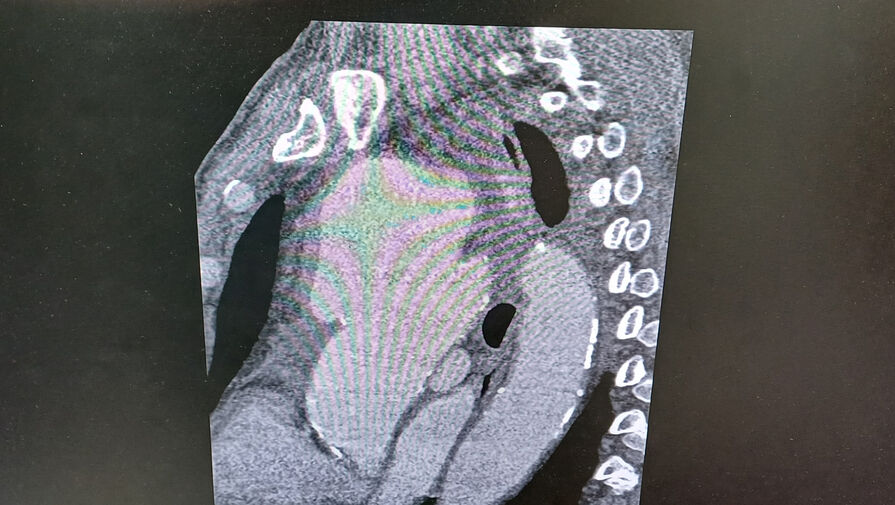

«Компьютерная томограмма подтвердила выпячивание аорты размером 9 на 9 сантиметров. Гигантская мешотчатая аневризма, больше, чем гусиное яйцо», — рассказал заведующий отделением №5 Рязанского кардиодиспансера Сергей Загородний.

По словам специалиста, аневризма сдавливала все близлежащие органы и ткани: трахеи, бронхи, верхнюю полую вену.